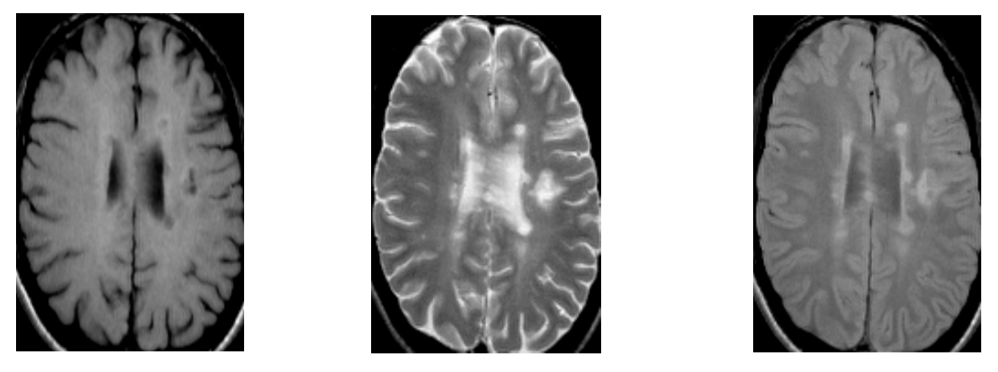

What is the pathology shown in these images?

What is the best weighting to view MS lesions?

[EXTRA]

What can be seen in this scan?

[EXTRA? Possible MCQ]